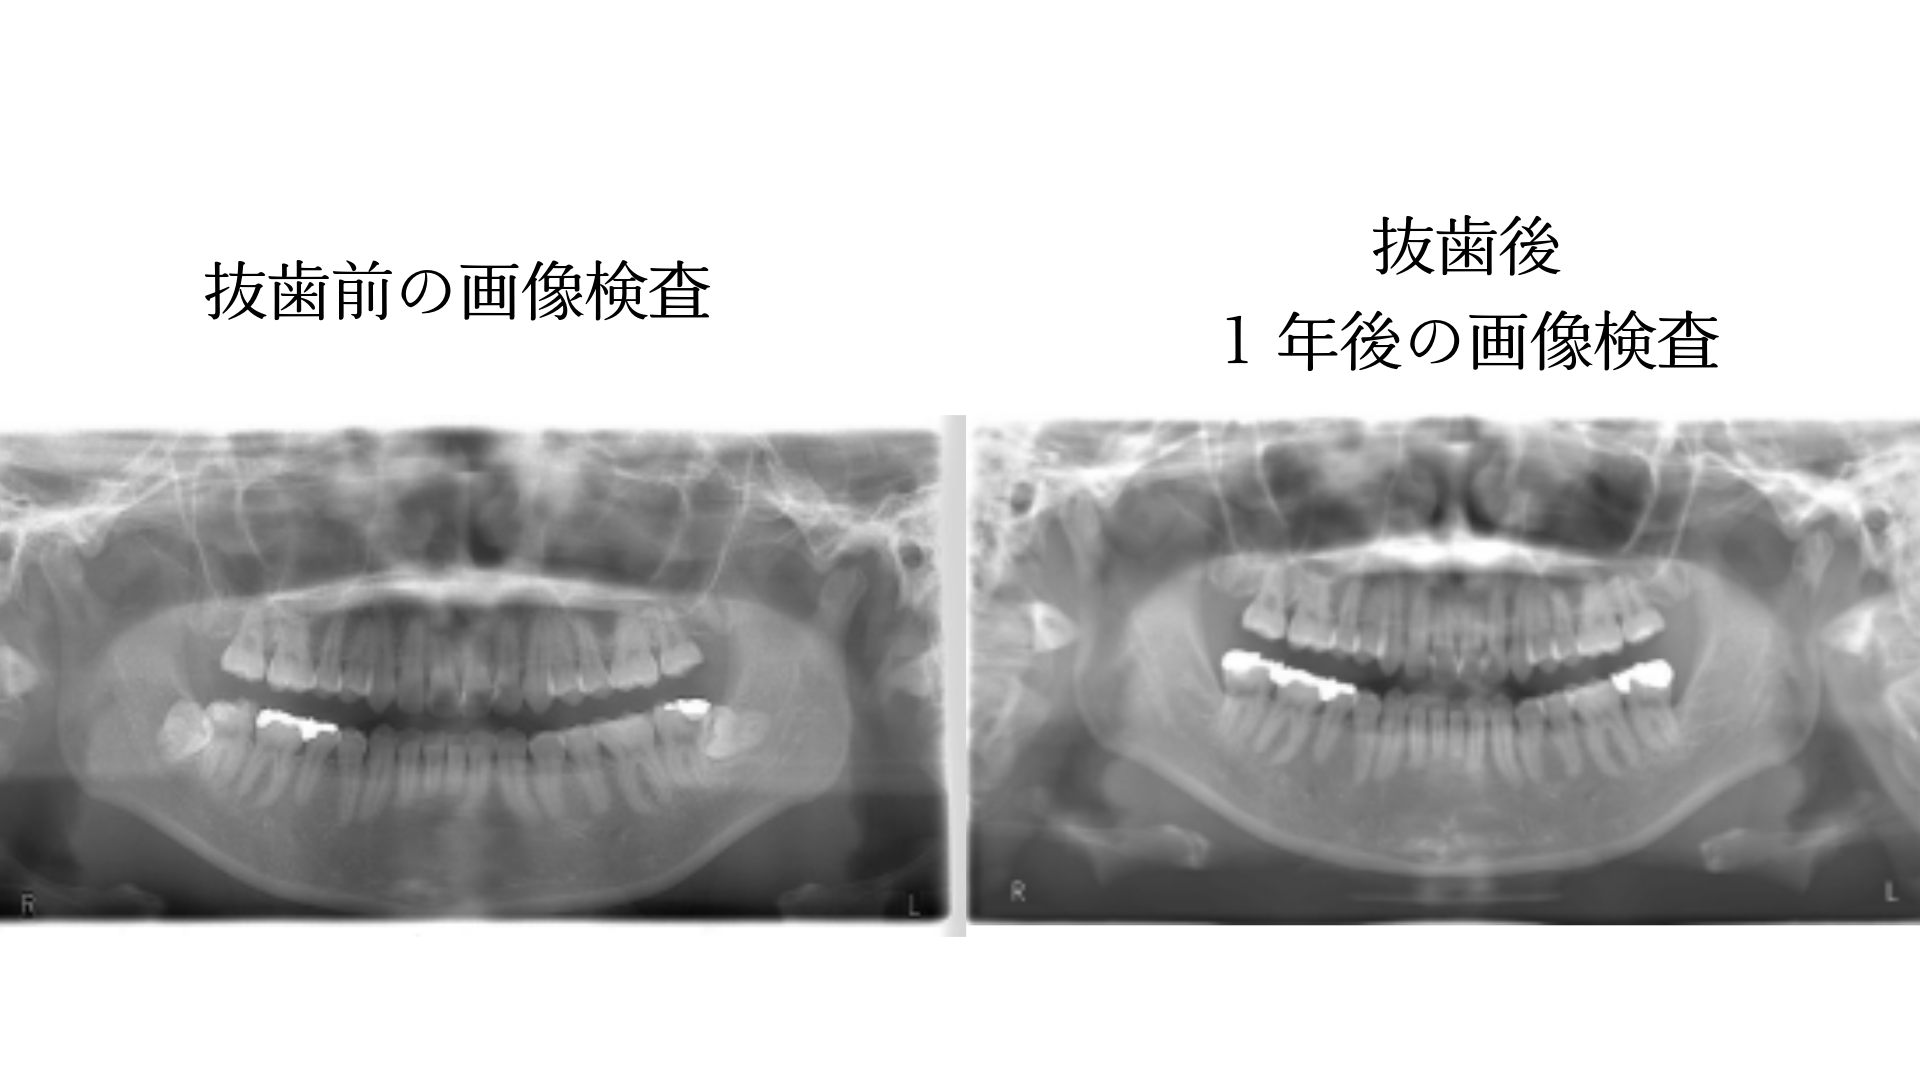

■ 長期的に経過を見守るアフターフォロー

大学病院では1ヶ月ほどで口腔外科の診療が終了することが多いですが、当院では専門医が常勤しているため、長期的な経過観察が可能です。 抜歯から1年後には、画像検査による最終評価も行います。

(保険診療:約5,000円)